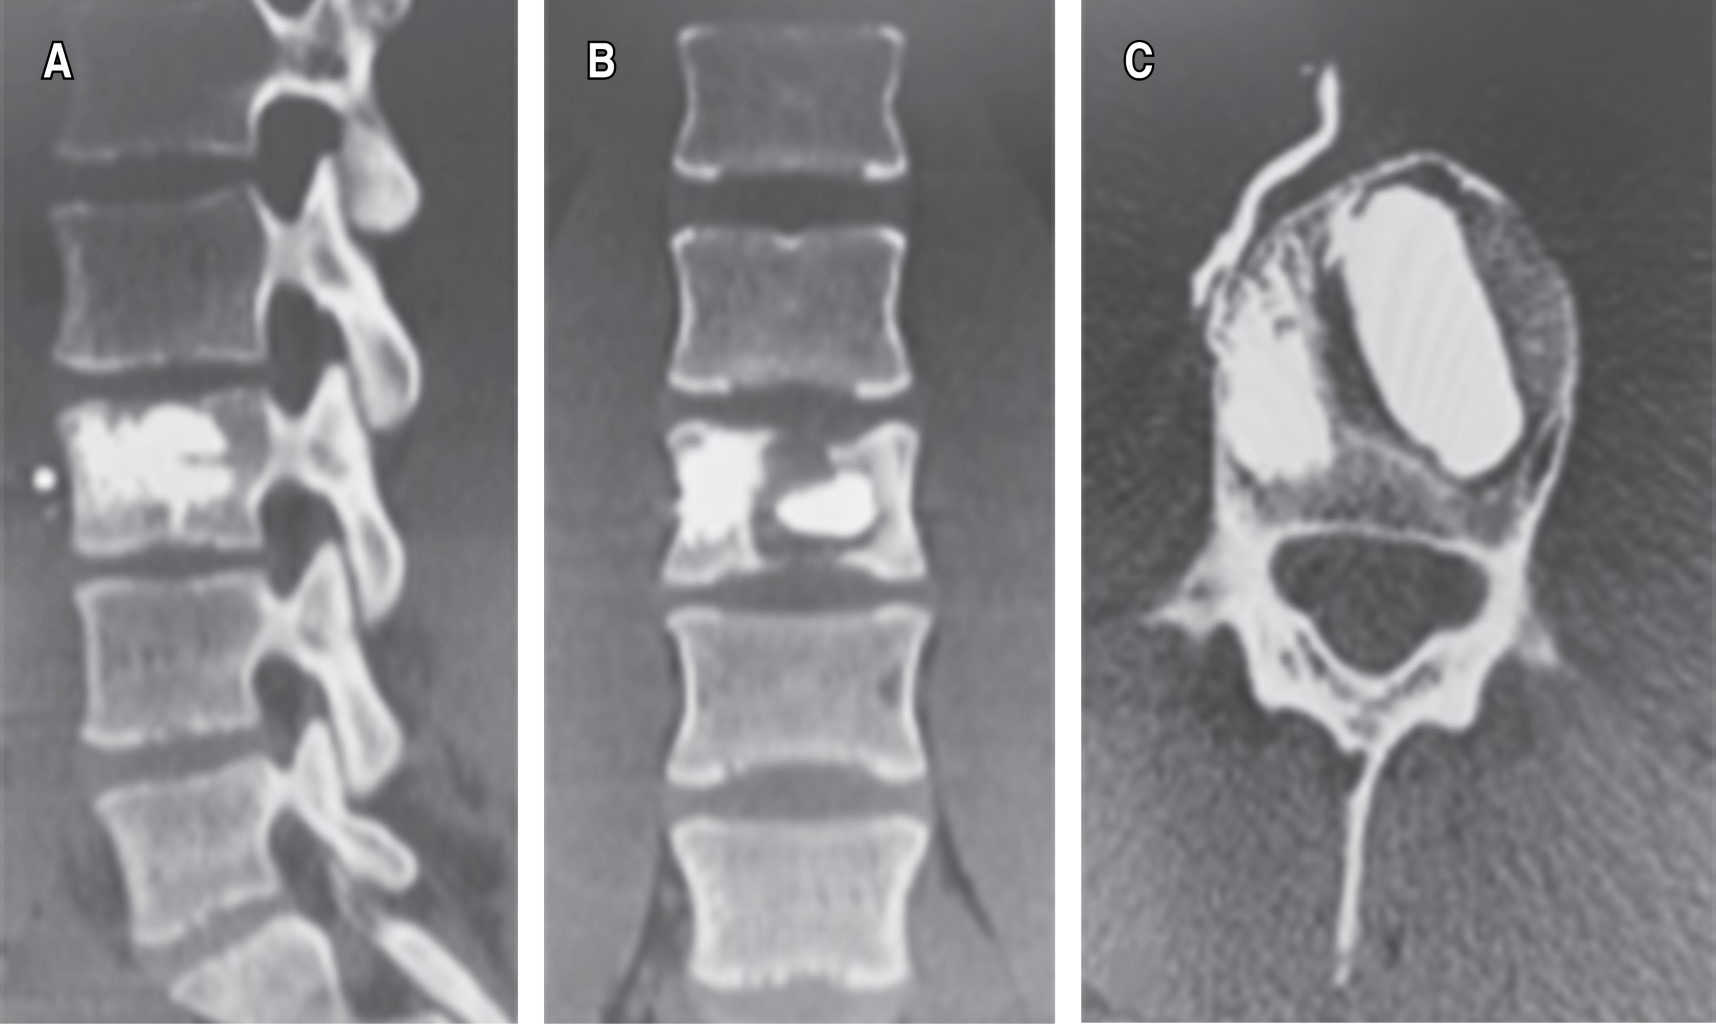

Plan: se decide manejo quirúrgico, cifoplastía L3 + toma de biopsia (Figuras 1 y 2).

El quiste óseo aneurismático de la columna vertebral es una patología benigna que genera destrucción ósea.1 Fue descrito por primera vez por Jaffe y Lichtenstein, en 1942, como una lesión intraósea y osteolítica, diferenciándolo de hemangiomas y otros tumores de células gigantes.2 Suelen crecer rápidamente, con hipervascularidad y proliferación reactiva de tejidos conectivos.3 Representan 1% de los tumores óseos primarios y afectan predominantemente en los primeros 20 años de vida.4,5 Presenta ligero predominio en mujeres. Después del osteoma osteoide y el osteoblastoma, es el tercer tumor óseo benigno más frecuente.6 Es una entidad poco frecuente, caracterizada por una agresiva destrucción ósea que conlleva a deformidad espinal, con significativas manifestaciones clínicas, derivadas del compromiso de estructuras neurales y tejidos blandos.1 Pueden provocar síntomas como dolor de espalda, déficit neurológico y fracturas patológicas.3 El dolor es la queja más común, principalmente en la zona lumbar, por las noches.6 La fisiopatología de los quistes óseos aneurismáticos es cuestión de debate, la mayoría de los autores proponen que se desarrolla como resultado de un edema intercelular causado por la lesión primaria que expande el estroma laxo circundante y permite la ruptura de los vasos hacia los microquistes bajo presión hemodinámica, provocando así un quiste lleno de sangre.4,7 Afectan principalmente a huesos largos, pero hasta 20% ocurre en la columna vertebral, predominantemente en elementos posteriores.4,8,9 La región cervical se ve comprometida en 30-40% de los casos, la columna torácica en 25-50% de los casos, y el segmento lumbar en 40-45%.2,10,11 El diagnóstico definitivo se obtiene a partir de hallazgos radiológicos e histopatológicos. Aparecen como lesiones líticas expansivas con márgenes escleróticos. Histológicamente aparecen como espacios llenos de sangre, separados por tabiques fibrosos, revestidos por fibroblastos e histiocitos, hay células osteoclásticas, sin atipia.4 En la tomografía y en la resonancia se pueden observar los niveles de líquido-líquido, lesiones con múltiples tabiques internos o colapso de cuerpo vertebral.6 Se debe realizar diagnóstico diferencial con el quiste óseo unicameral, tumor de células gigantes, osteosarcoma telangiectásico, condroblastoma y el osteoblastoma.12